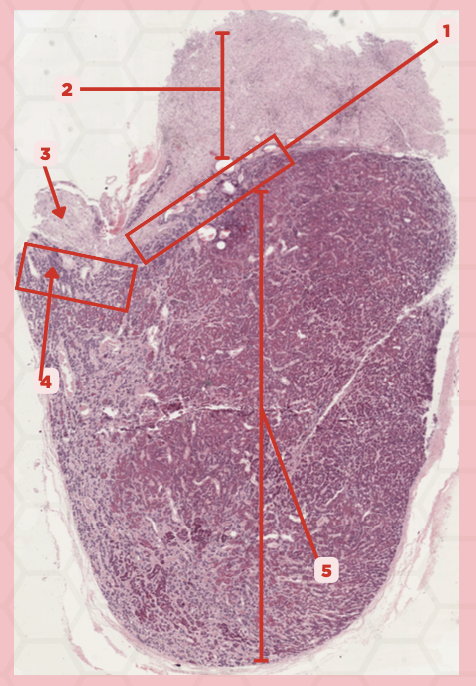

Pituitary

Identify the specimen.

Anterior Lobe

Identify the structure labeled as 1.

Posterior Lobe

Identify the structure labeled as 2.

Intermediate Lobe

Identify the structure labeled as 3.

Pars Tuberalis

Identify the structure labeled as 4.

Pituitary Stalk

Identify the structure labeled as 5.

Neural Ectoderm

What ectoderm is #2  derived from?

Oral Ectoderm

What ectoderm #1, #3, & #4 derived from?